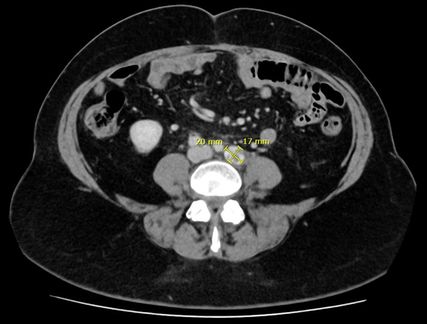

Abb. 1:Persistente parailiakale Lymphknotenmetastase nach sechs Zyklen Chemotherapie und zwei Zyklen Immuntherapie

Basierend auf den Ergebnissen der Phase-III-Studie DUO-E wurde eine Erweiterung der systemischen Therapie empfohlen. In DUO-E hatte die Zugabe des PARP-Inhibitors Olaparib zu dem PD-L1-Inhibitor Durvalumab im Sinn einer onkologischen Vierfachtherapie bei non-dMMR-Karzinomen zu einer signifikanten Verlängerung des progressionsfreien Überlebens geführt.1 Die Kombinationstherapie wurde von der Patientin ohne Hinweis auf „immune-related adverse events“ (irAEs) gut vertragen. Serologisch zeigte sich eine Remission mit normwertigen Tumormarkern und radiologisch eine stabile Erkrankung mit größenkonstanten Lymphknotenmetastasen. Die Abbildungen zeigen den Zustand nach sechs Zyklen Chemo- und zwei Zyklen Immuntherapie (Abb.1) sowie nach sieben Zyklen Immuntherapie (Abb.2). Die Patientin befindet sich aktuell weiterhin unter laufender dualer Erhaltungstherapie mit Durvalumab – zuletzt Zyklus 10 – und Olaparib.